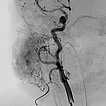

In the transarterial control angiography via the 4F diagnostic catheter, the infantile hemangioma is not perfused anymore. The typical DSA image of a “defoliated tree” is now shown.

Overview angiography via the common carotid artery after removal of the venous blocking balloon displays a virtually completely devascularized infantile hemangioma. The intracerebral circulation is normal.

Only 6 days after embolization, the subcutaneously located infantile hemangioma has decreased substantially in volume (AP view). The overlying skin did not discolor. The patient was asymptomatic from this point on, and the infantile hemangioma completely regressed within 3 months without further therapy.

Deeply situated infantile hemangiomas may cause local symptoms via the space-occupying effect due to their size. If medical therapy with propranolol (gold standard) alone does not show sufficient effect, invasive therapy (embolization or resection) may still be indicated in rare circumstances. The peculiarity of this case was the high-grade stenosis of the venous outflow, which probably led to insufficient regression via venous congestion. However, this stenosis could be used during embolization to simultaneously block out the venous drainage and avoid unintended dislocation of the embolic agent to the venous side. After successful embolization, infantile hemangiomas tend to regress rapidly because they are cut off from the arterial blood supply and thus from hypervascularization.